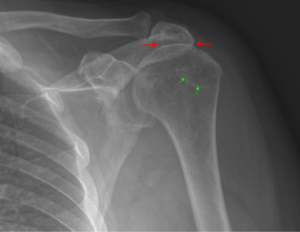

Impingement is when the top of the humerus bone of the upper arm impinges upon one or more of the tendons of the rotator cuff, literally fraying it. See the image below.